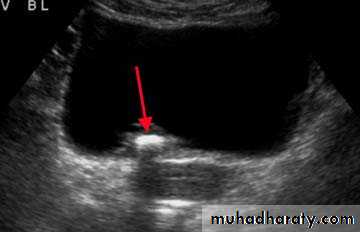

Calcification of the urinary bladder wall